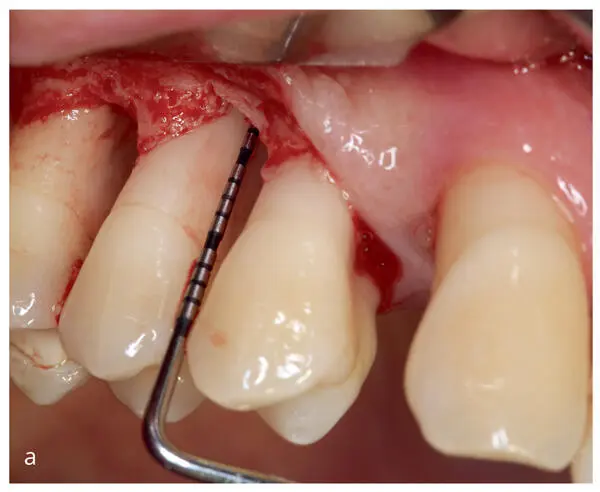

Figs 2-7a to eRepresentative images of the corrective therapeutic phase. (a) Intrabony three-wall defects subjected to regenerative periodontal therapy at maxillary right second premolar and first molar. (b) Wound closure upon application of enamel matrix derivatives onto the root surfaces. (c and d) Minimally invasive access to the three-wall intrabony defect at the mandibular right first molar. (e) Wound closure upon application of enamel matrix derivatives onto the root surface.